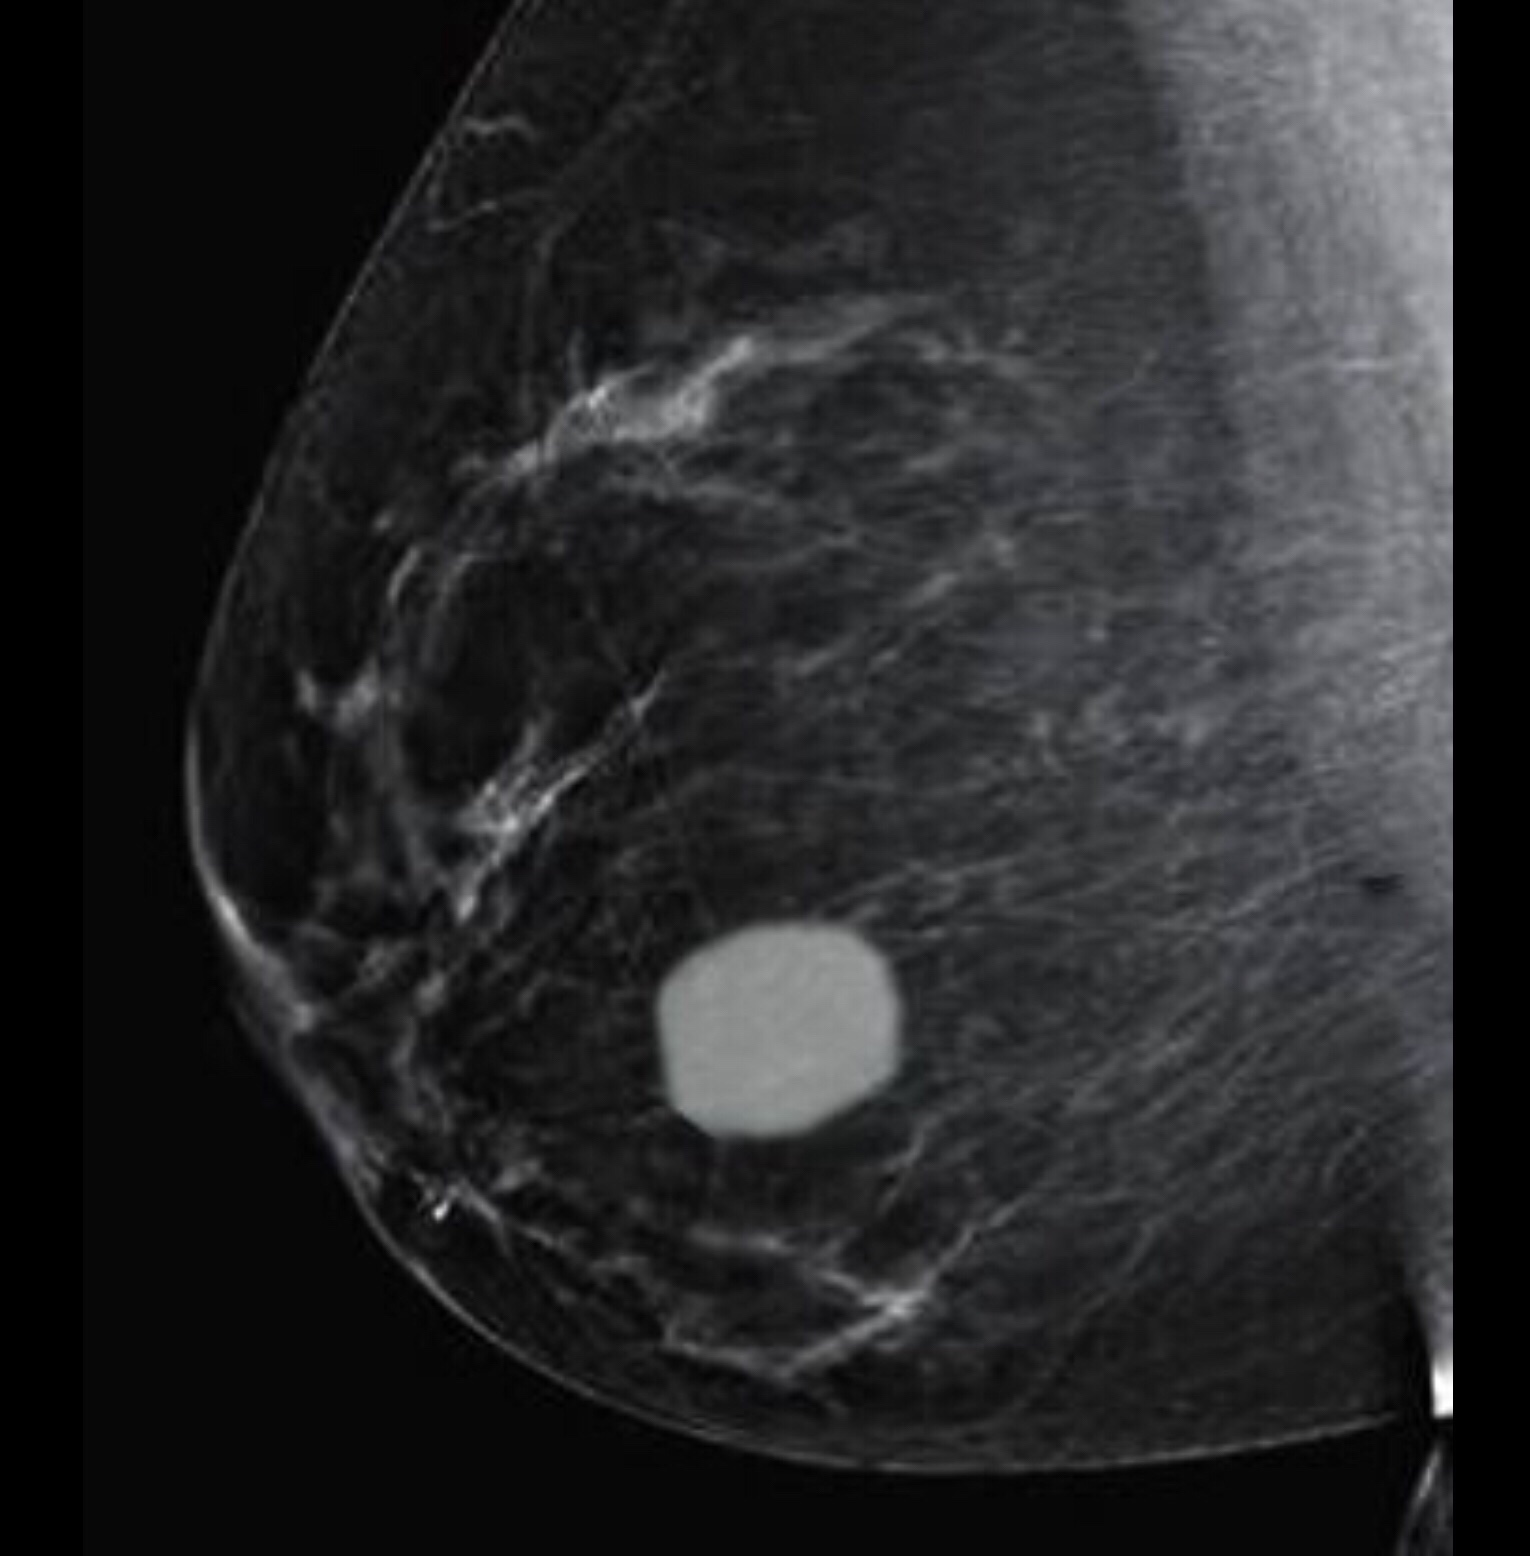

Simple Breast cyst: cysts are fluid containing cavities and are very well seen on the Ultrasound of the breast. But this is how they would appear on a mammogram. This thin walled cyst is accompanied by small smooth round to oval calcifications suggesting a benign lump.